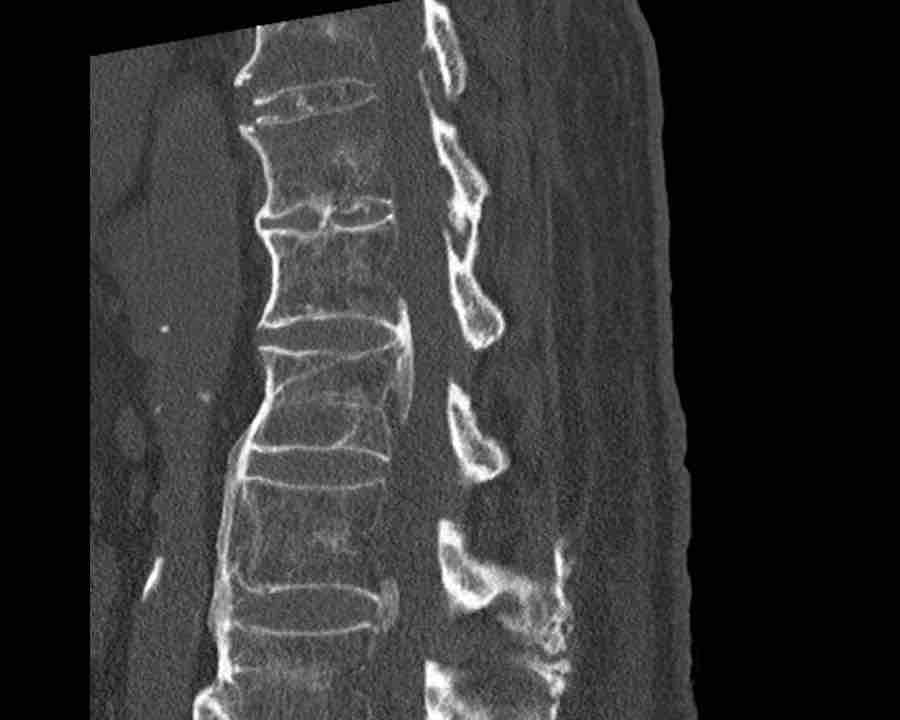

Scroll through images.

What are the findings?

Findings

- C injury? No.

- Signs of a rigid spine?

Yes, so be aware of potentially very subtle B3 injury. - A subtle fracture on the anterior vertebral body is seen (arrows).

Conclusion

Injury type B3.